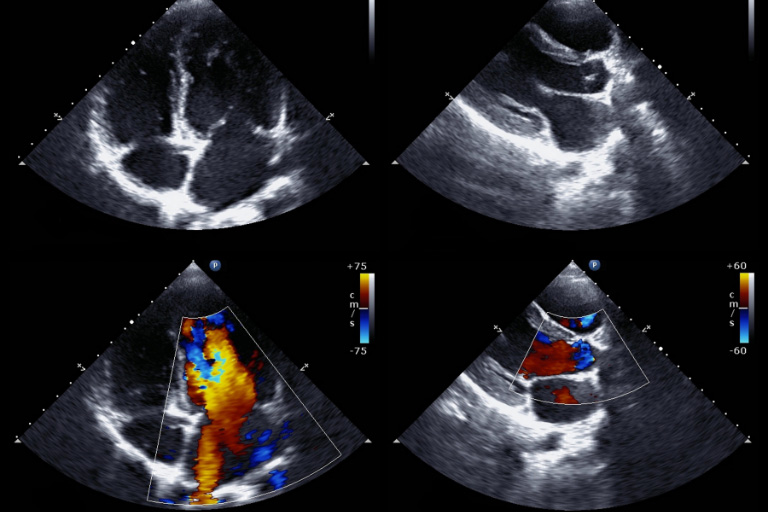

Auf unsere Geräte können Sie sich verlassen. Unsere Ultraschallgeräte für die Kardiologie kommen voll ausgestattet mit zahlreichen Sonden und Funktionen, die Abläufe in Ihrer Praxis optimieren. TEE-Sonden für die transösophageale Echokardiographie und Sektorsonden für transthorakale Echokardiographie gehören bei unseren Ultraschallgeräten für die innere Medizin zur Standardausstattung. Mit intelligenten Funktionen wie 3D-Programmen, Farb-Doppler-Einstellungen und Ablaufprotokollen für die Belastungsechokardiografie überzeugen unsere medizinischen Ultraschallgeräte in jedem Szenario.